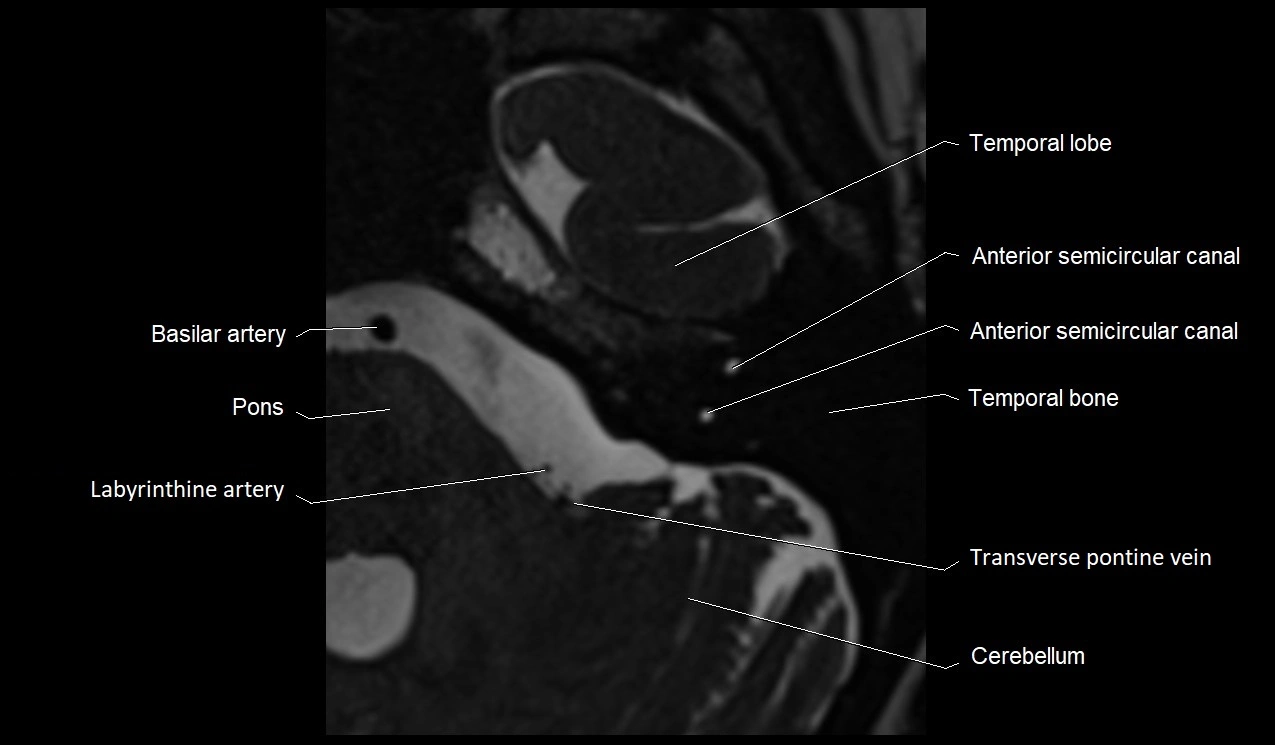

• Best visualized on high-resolution T2-weighted 3D MRI sequences (e.g., FIESTA or CISS)

• Seen as a hypointense (dark) line running from the brainstem at the pontomedullary junction, traversing the prepontine cistern, and entering Dorello’s canal under the petrosphenoidal ligament, then into the cavernous sinus, and finally the orbit